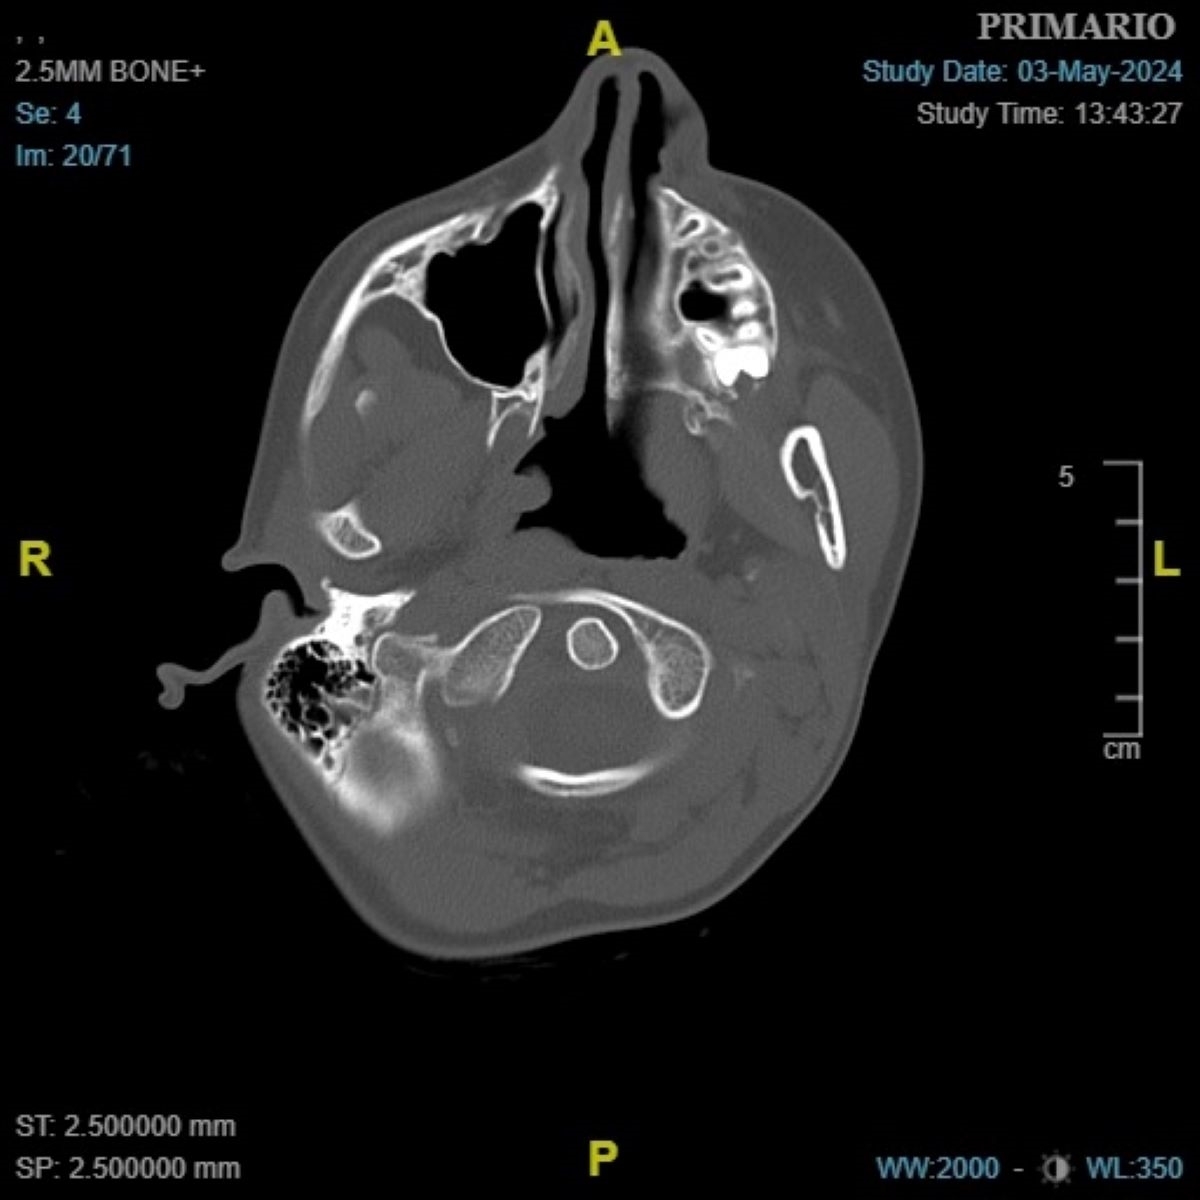

Niña de 9 años de edad, sin antecedentes de interés, que ingresa por cuadro de fiebre, adenitis cervical y tortícolis para la administración de antibioterapia (cefazolina, clindamicina), antiinflamatorios y corticoides i.v. Durante el ingreso presenta desaparición de la fiebre, disminución del tamaño de la adenopatía y mejoría discreta del dolor, pero persiste la tortícolis rígida, por lo que se le realiza una radiografía lateral de faringe, que no es concluyente. Se completa el estudio con TC cervical (Figura 1 y Figura 2).

Figura 1. TC (corte axial): la distancia entre el arco anterior del atlas y la apófisis odontoides no supera los 3 mm.